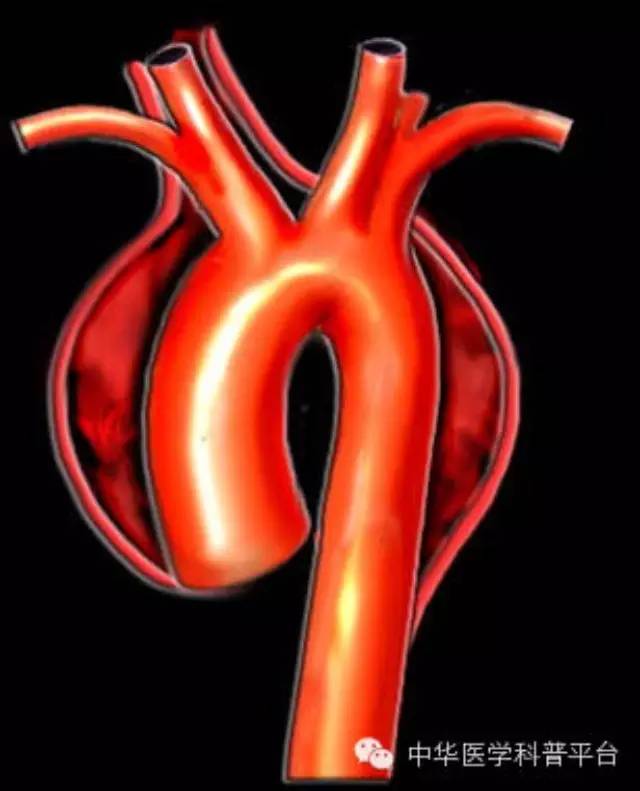

主动脉夹层是一种相对少见但极为严重的疾病,医学上将其定义为主动脉腔内的血液通过内膜的破口进人主动脉壁囊样变性的中层而形成夹层血肿,并沿着主动脉壁向周围延伸剥离的严重心血管急、危、重症。

【正常的人体动脉血管由3层结构组成,内膜、中膜和外膜,3层结构紧密贴合,共同承载血流的通过。主动脉夹层时血液通过主动脉内膜裂口,进入主动脉壁并导致正常动脉壁的分离。】